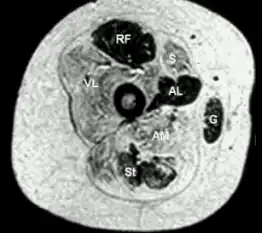

Transverse section from child with central core disease -

Histopathologic appearance of typical central core disease: NADH-TR, transverse section from the rectus femoris. Marked predominance of dark staining, high oxidative type 1 fibres with cores affecting the majority of fibres. Cores are typically well demarcated and centrally located (→), but may occasionally be multiple and of eccentric location.